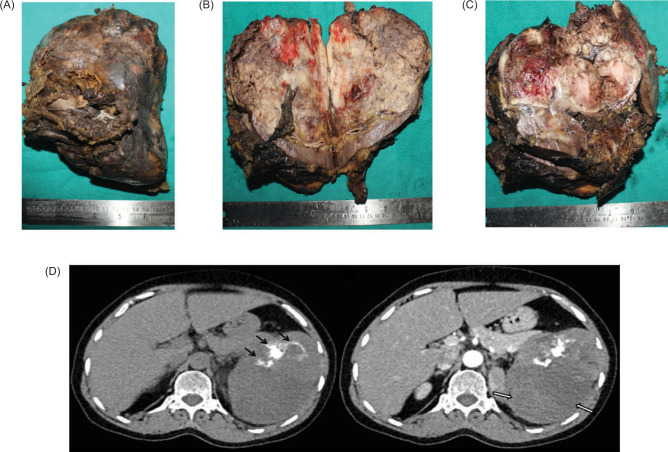

Chromophobe renal cell carcinomas (ChRCCs) have a good prognosis and comprise approximately 5-7% of renal cell carcinomas (RCCs). The sarcomatoid differentiation in RCC is found in around 5-10% of cases; however, in ChRCC, it is much less than in other RCCs and poorly responds to chemotherapeutic agents. A study by de Peralta-Venturina et al. found 9% sarcomatoid differentiation in chromophobe RCC. We present the case of a 58-year-old female with a left abdominal mass diagnosed as ChRCC with the existence of sarcomatous differentiation including osteosarcomatous and chondrosarcomatous, which are of adverse prognosis. Osteosarcoma-like divergent differentiation in RCC is extremely rare, with limited documented cases. It should be carefully considered in evaluating and managing renal masses due to its potential impact on clinical outcomes.